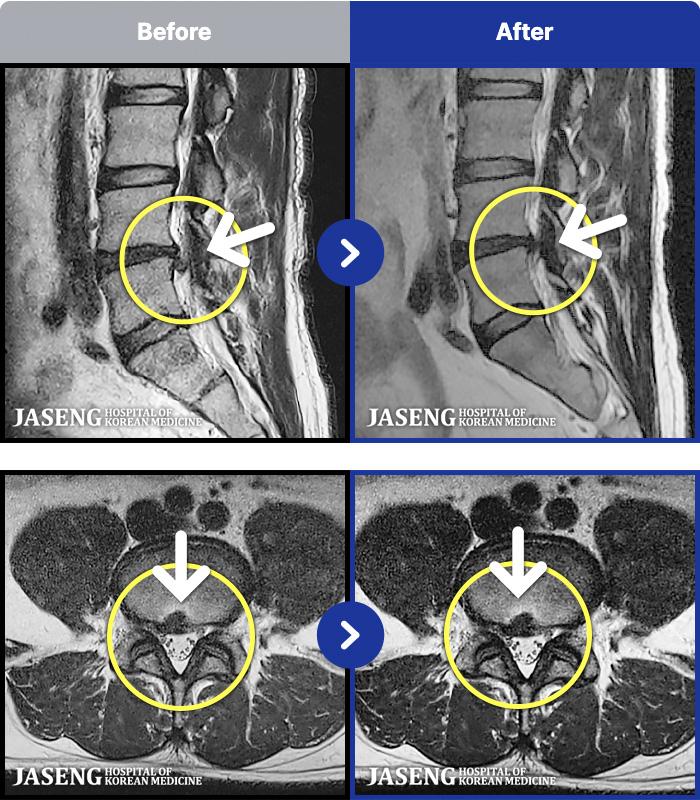

MRI ġ

MRI ũ ʸ Ȯϼ.